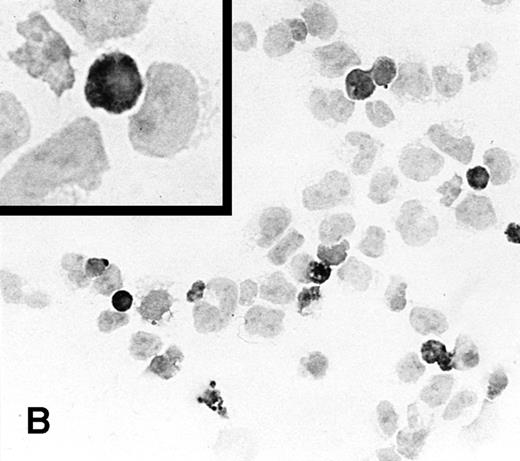

Both transduced and selected NK-92 and YT cells expressed a high number of IL-2 mRNA copies as determined by QC-RT-PCR (Fig5; TR-IL-2-NK-92 cells, 1,400 copies/ng total RNA; TR-IL-2-YT cells, 2,000 copies/ng). In contrast, parental cells expressed a marginally small number of IL-2 mRNA copies (P-NK-92 cells, 0.304 copies/ng total RNA; P-YT cells, 0.117 copies/ng).

Expression of IL-2 mRNA in the parental or IL-2 gene–transduced and selected NK cell lines by QC-RT-PCR. Total RNA extracted from NK cell lines (100 ng from parental cells, 1 ng from IL-2 gene–transduced cells) was reverse-transcribed and amplified using primers specific for IL-2. Southern hybridization was performed with radiolabeled cDNA for IL-2 to confirm the identify of the PCR product. The ratio of cpm in the internal control to cpm in cellular RNA was plotted to calculate the number of copies of IL-2 mRNA/ng total cellular RNA (not shown). (A) NK-92 cells, (B) YT cells.

Expression of IL-2 mRNA in the parental or IL-2 gene–transduced and selected NK cell lines by QC-RT-PCR. Total RNA extracted from NK cell lines (100 ng from parental cells, 1 ng from IL-2 gene–transduced cells) was reverse-transcribed and amplified using primers specific for IL-2. Southern hybridization was performed with radiolabeled cDNA for IL-2 to confirm the identify of the PCR product. The ratio of cpm in the internal control to cpm in cellular RNA was plotted to calculate the number of copies of IL-2 mRNA/ng total cellular RNA (not shown). (A) NK-92 cells, (B) YT cells.